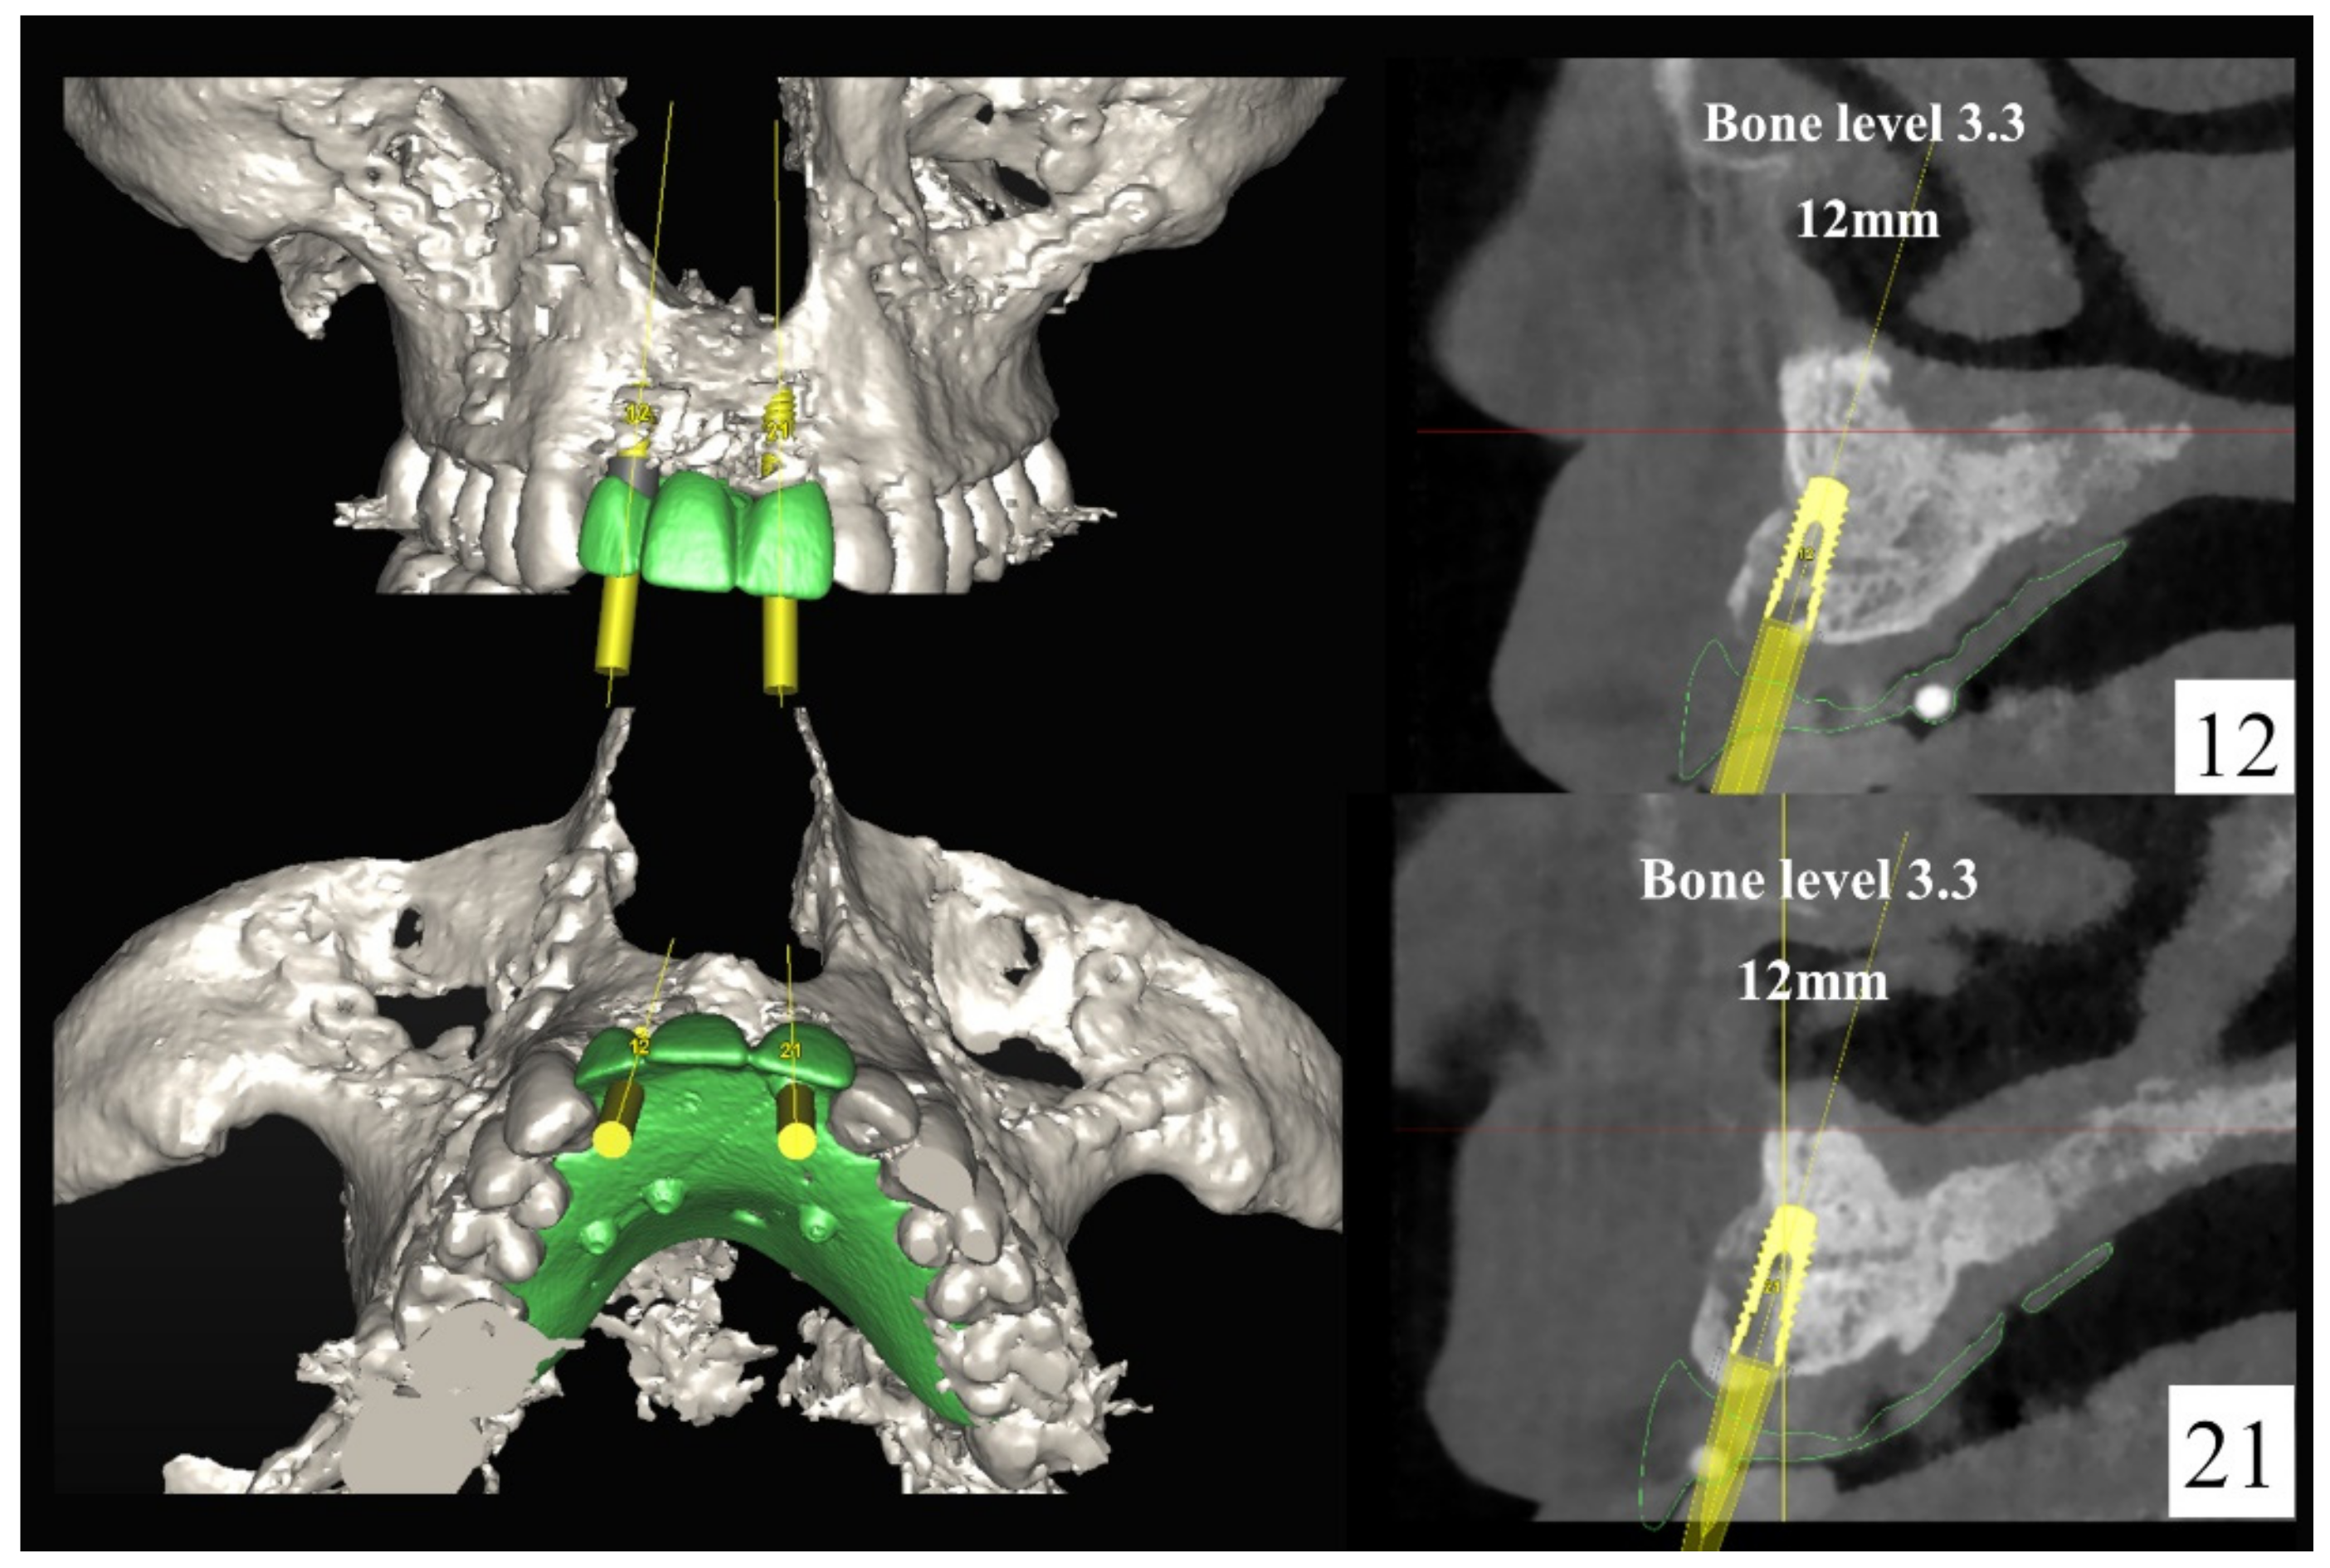

The number, the length, the diameter and the placement of computational virtual implants were determined with respect to the design of the final prosthesis the available residual bone volume and the anatomical limitations according to the previously described technical procedure (Figure 3, Figure 4, Figure 5 and Figure 6).

Figure 3.

Three-dimensional (3D) CBCT scan images with the patient wearing the planned prosthesis and 3D images of the prosthesis equipped with integrated radiopaque reference spheres scanned separately.

Figure 4.

Planning of the number, the diameter, and the axis of the implant with respect to the design of the final prosthesis.